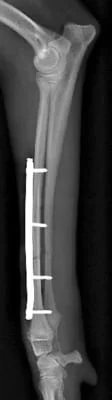

左前肢

左前肢は中和プレートのみなので2期癒合を目指します。

*術後早期は外固定を併用します。

同じく術後19日目 左前肢

左前肢は2期癒合を目指すので、術後2,3週間前後のレントゲンでは

周囲に仮骨形成を認め、また、

骨折部の骨が溶けているように見えます。

これは骨再構築(骨芽細胞、破骨細胞、両方の活動によるもの)

されて起こる現象なので問題ありません。

インプラントの折損、明らかな動揺は認めません。